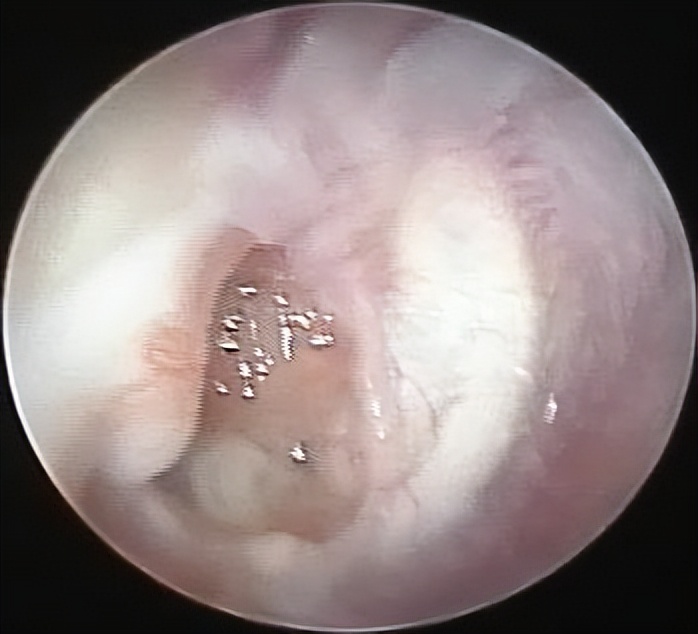

入院检查后发现谢女士的中耳有大量的钙化斑和肉芽组织,这是导致她反复流脓和听力极差的原因。这次做的是全麻耳内镜中耳炎微创手术,术中清理了钙化组织和肉芽后发现患者的听骨链是断裂的,术中取出了残留的锤骨和砧骨。镫骨是完整的,活动可。用人工听骨重建了听骨链,自体耳屏软骨修补了鼓膜。整个的手术用时约70分钟,非常的顺利。术后查房患者感觉听力有提高,无手术相关的并发症。